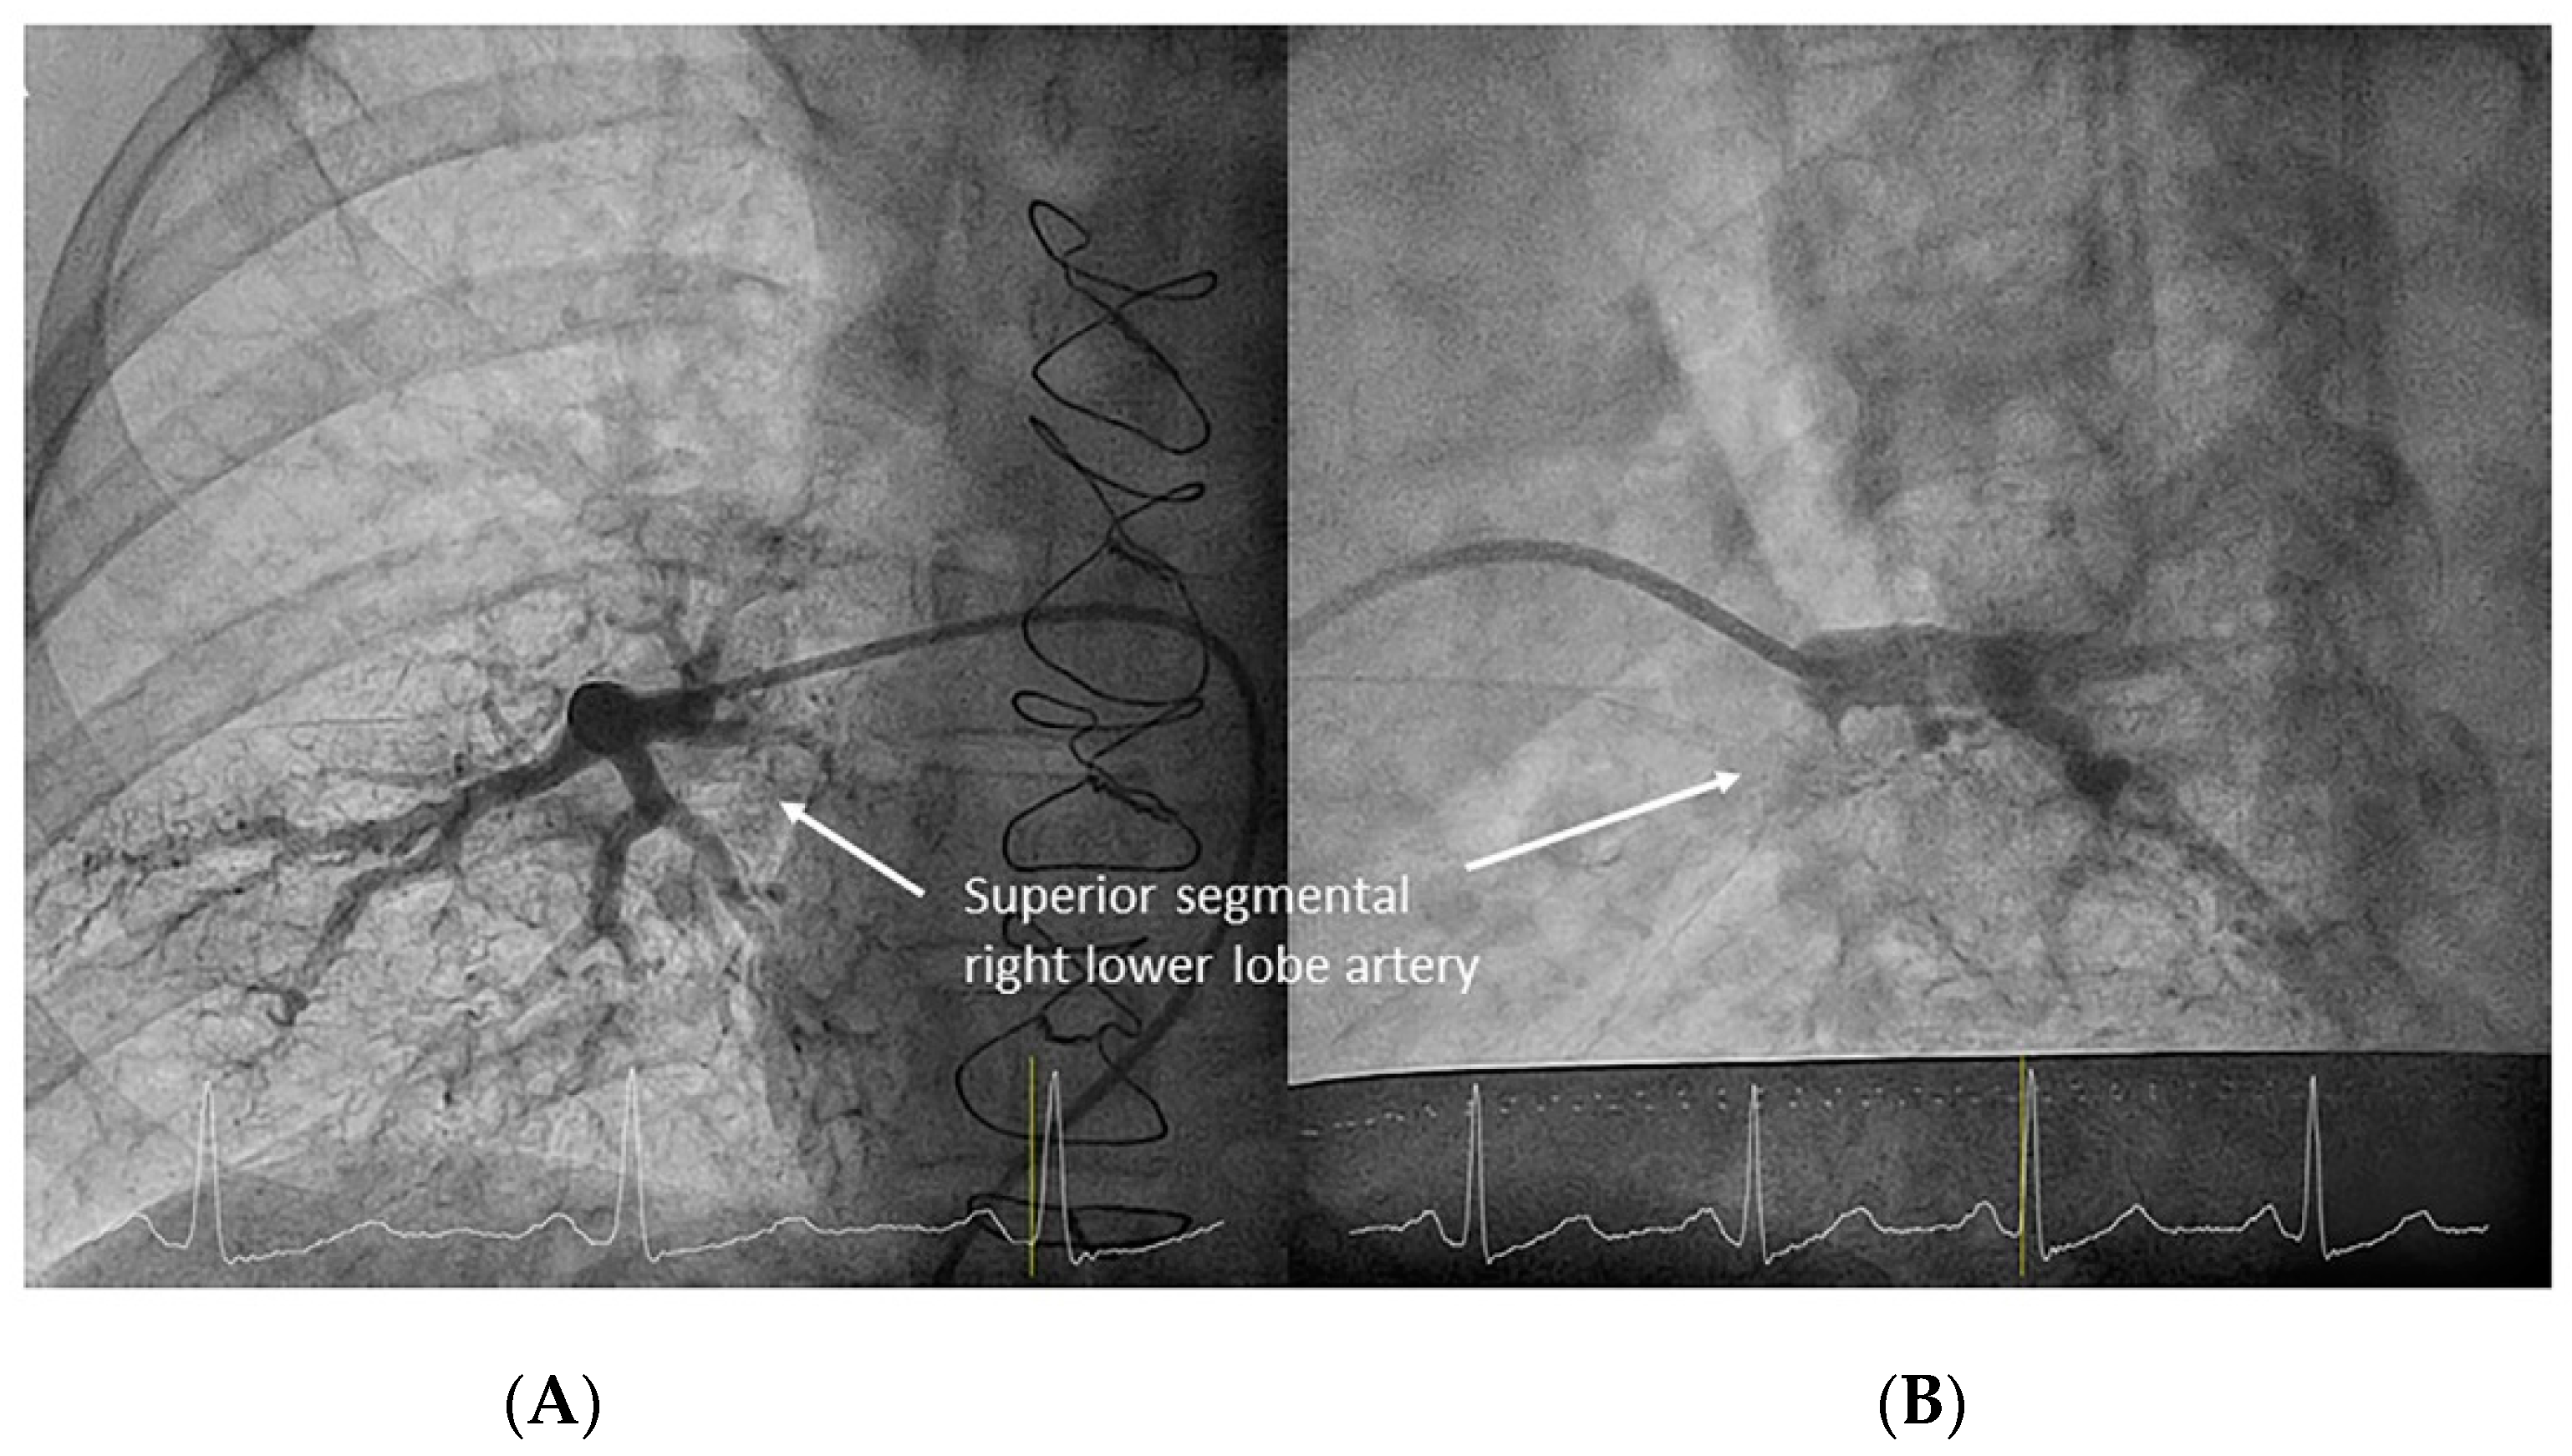

- Right lower lobe. The lateral projection and the MP are the best choices to canalize the two trunks of the basal pyramid and the superior segmental artery (A6). Use the AP and lateral views to assess the four segmental basal branches (Figure 32) and the lateral projection to display the superior segmental artery (A6) (Figure 16 and Figure 17).